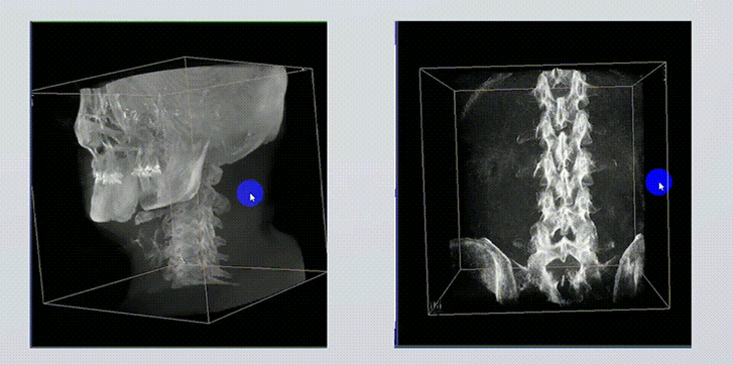

1、術(shù)中實(shí)時(shí)三維成像

術(shù)中三維成像和橫斷面圖像提供多角度的手術(shù)診斷信息,輔助醫(yī)生進(jìn)行術(shù)中評(píng)估判斷,諸如骨折復(fù)位情況和內(nèi)植入螺釘?shù)某叽绾臀恢?,輔助手術(shù)更好地完成。

2、三維成像視野大

提供更大的術(shù)中三維成像視野,采集更多圖像信息,可一次拍全全段頸椎、全段腰椎、七節(jié)胸椎、雙側(cè)骶髂關(guān)節(jié)、股骨頭及單側(cè)盆骨。